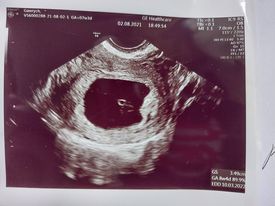

Czesc jestem tu od tygodnia i wiele dobrych słow usłyszałam od dziewczyn i porad.Nietety okazało sie najgorsze.Byłam potwierdzic prywatnie u innego lekarza co dzieje sie z ciążą.Jestem w 7tyg. i p.doktor powiedzial,że nie widzi serduszka i bardzo mu przykro bo ciążą nie żyje.Dał mi skierowanie na zabieg.Jak to wszystko wygląda i jak długo sie jest w szpitalu.Czego mam sie spodziewac? Narazie probuje sie oswoić z tą myślą ,że dzidziuś sie nie rozwinął.Strasznie mi cieżko pierwszy raz jestem w takiej sytuacji.To moja druga ciąża.Może juz wiek juz niestety nie ten i dac sobie spokój.Ilona 40lat. :,(

• 7tydzien 2.jpg

7tydzien 2.jpg

11,6 KB · Wyświetleń: 129

A masz regularne miesiączki? Badałaś betę? Jaka jest wielkość zarodka? Niestety te zdjęcia są zbyt małe i nie jestem w stanie tego zobaczyć. Nie chcę Cię na nic nastawiać, ale moim zdaniem lekarz się trochę pospieszył z tym skierowaniem.